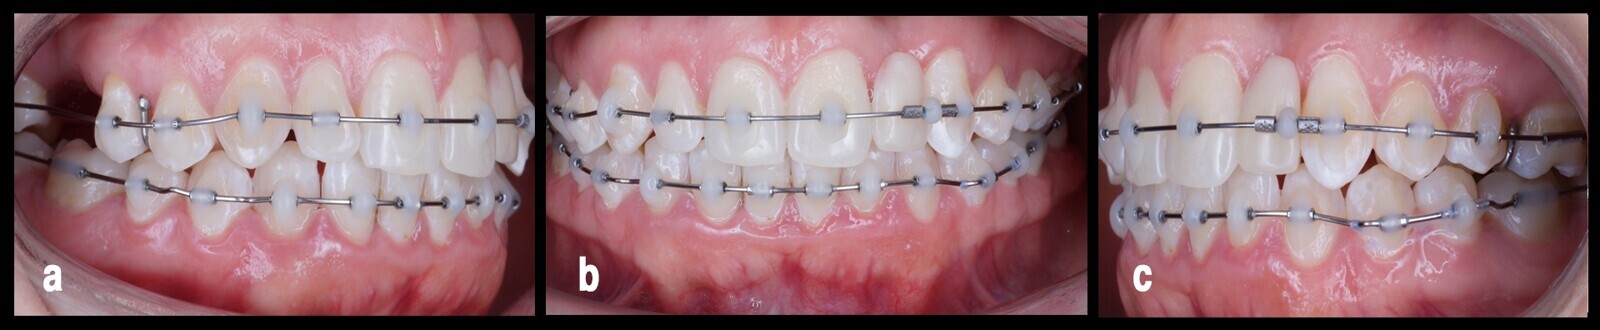

Una vez conseguida la adecuada nivelación con corrección de la sobremordida, se procedió al tratamiento del arco inferior. Esta estrategia está dirigida a ofrecer la mínima invasión posible para el paciente, logrando la corrección por fases de tratamiento guiadas en lograr los objetivos del diagnóstico inicial (Fig. 5).

Figura 5. El tratamiento del arco inferior, después de conseguir una adecuada nivelación y corrección de la sobremordida en el arco superior desde tres vistas (a, b, c).